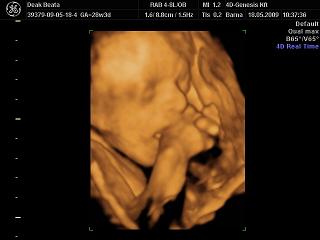

Dbea! Nagyon klasszak a fotók a bébiről, olyan édes, ahogy szopizza az ujját. Klassz a konyhabútor, szépek lesztek!